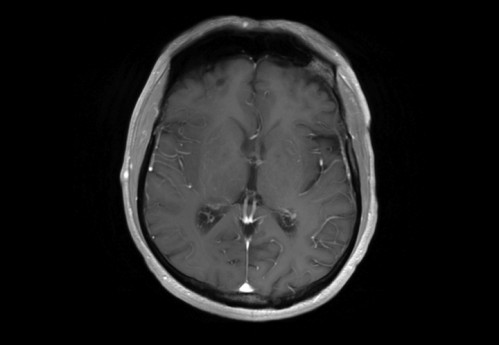

Sie behandeln einen 48-jähriger Mann, von Beruf Architekt. In der Anamnese erfahren Sie, dass er leidenschaftlich Gitarre spiele und er berichtet, dass ihm seit zwei Wochen in der rechten Hand die nötige Koordination fehle. Auch das Plektrum würde ihm immer wieder aus den Fingern gleitet.

Eine Magnet-Resonanz-Tomografie (MRT) des Kopfes wurde durch den ambulant behandelnden Neurologen bereits veranlasst.